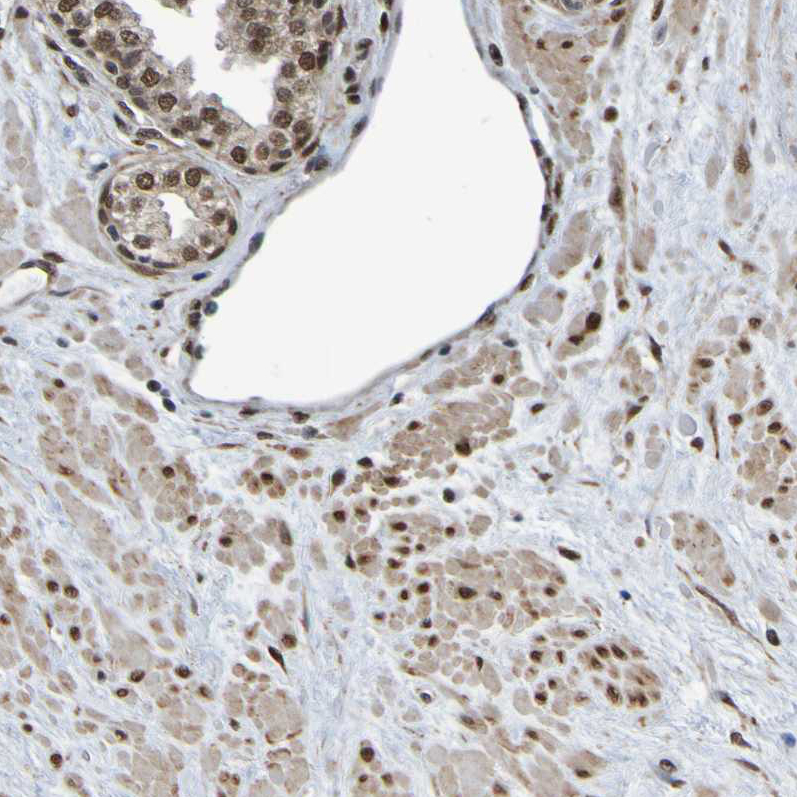

Immunohistochemical staining of human testis shows strong nuclear positivity in cells in seminiferous ducts.